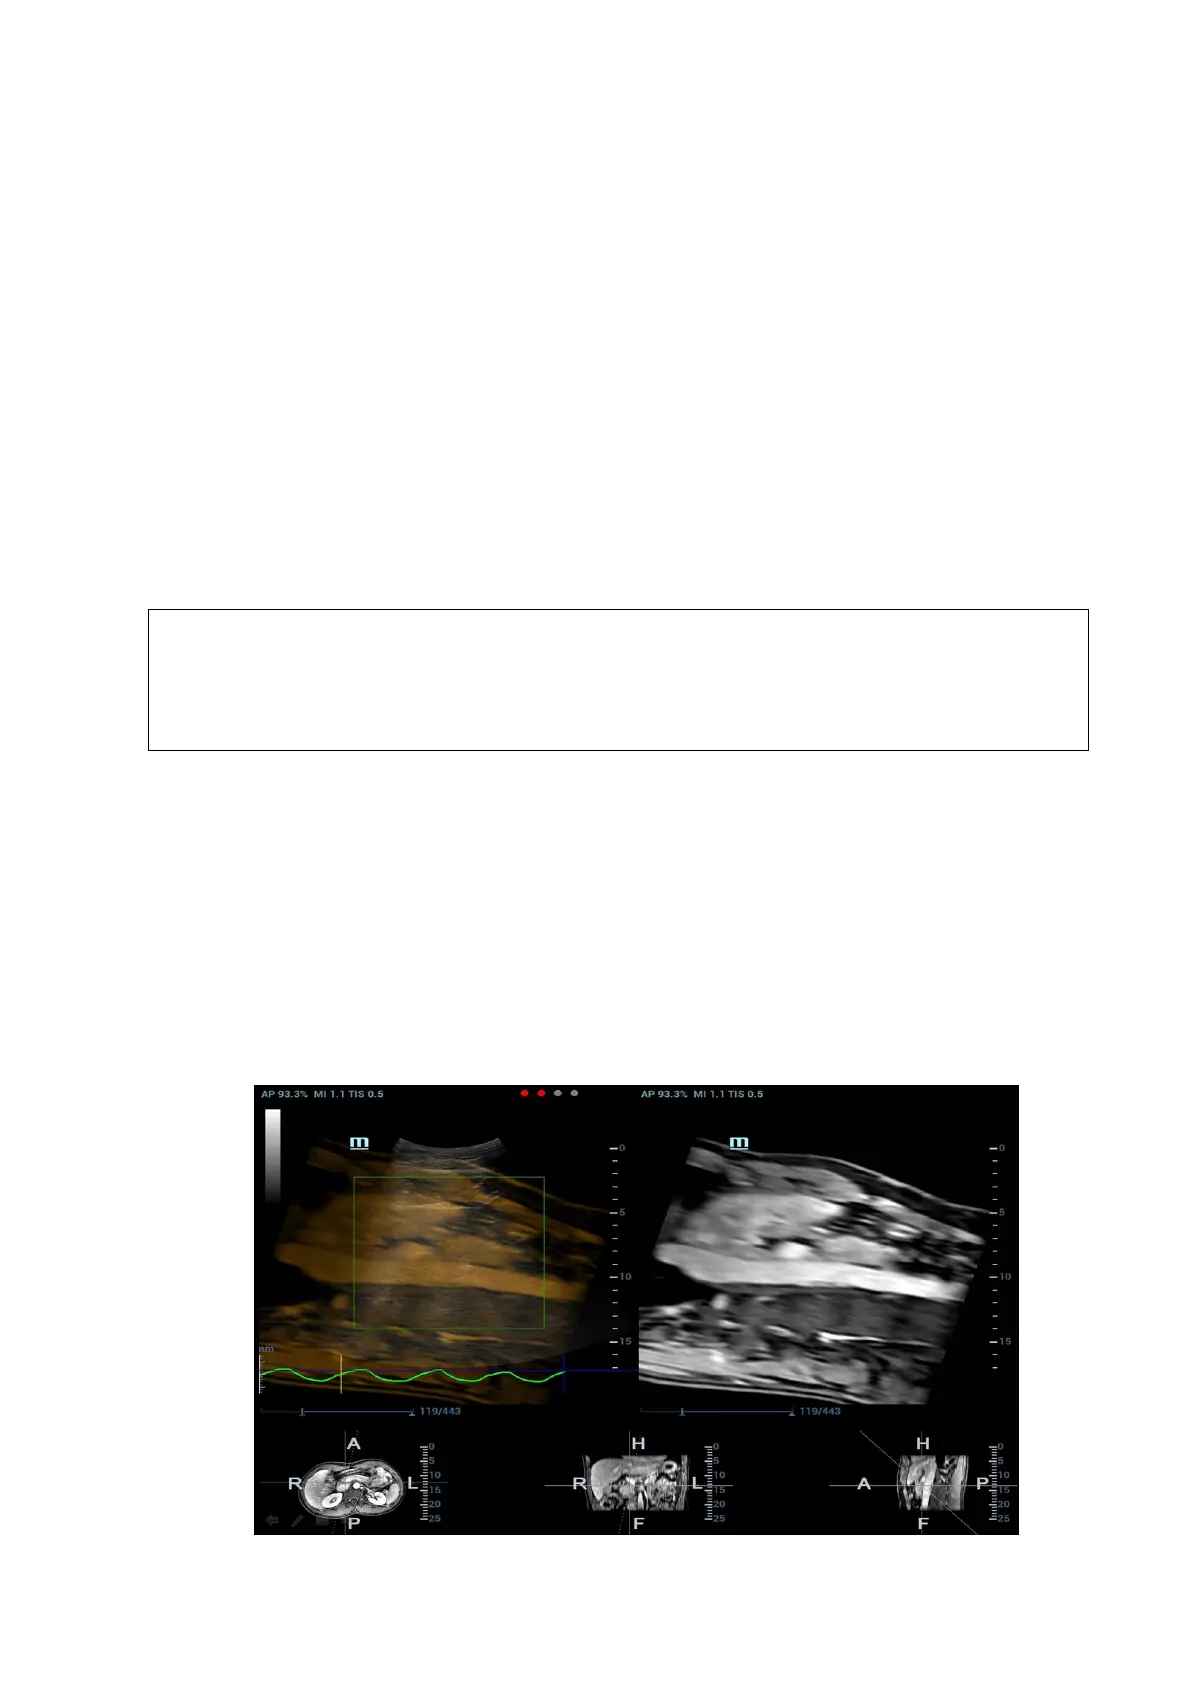

Respiration Compensation sets a motion model for the movement regularities of the liver, and

compensates the CT image in real time. The fusion dynamic accuracy is enhanced apparently.

1. Enter Fusion Imaging mode. Tap [Display Resp Curve] to activate it (it becoming highlighted by

default). The respiratory curve appears on the image.

2. Keep the patient breathing regularly. Tap [Capture US&Resp] to capture the cine until the

respiration curve becomes stable. Keep the probe still when capturing the cine. The progress

bar appears on the screen. The ultrasound cine plays automatically after the capturing is

finished.

Note: the Ultrasound System selects one premium phase of respiration curve automatically

after the capturing is finished. It is prepared for the motion modeling. You can set the start

frame and end frame to select one phase of the respiration curve.